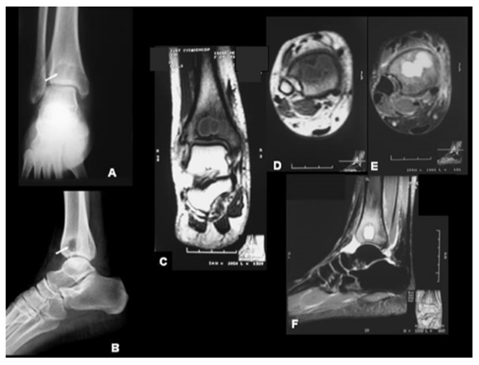

Diagnosis related to musculoskeletal sepsis can be identified with the help of the magnetic resonance imaging (MRI). Although it is pricy it should be preferred when the diagnosis of osteomyelitis is in indeterminate. In case of acute osteomyelitis image appeared abnormal marrow with decreased signal intensity in affected area. MRI also help the surgeon to plan the optimal surgical management, which showing the critical adjacent structure to avoid illness and further complication (Figure 4). The MRI finding are depends up on weighted T1 or T2 pulse sequence on the disease stage. Imaging principal and different pulse sequence can be used in the evaluation of musculoskeletal system. Arrows around the Image A and b represent classic presence of an abscess image C indicated the Axial T1-weighted MRI scan showing an intramedullary lobulated lesion, with a defined outline. While image D, Indicate the T1-weighted and T2 fat-suppressed Coronal MRI scans displaying marrow involvement and image F represents the MRI scan showing hyperintense circular and precise lesion. Computed axial tomography (CAT) also have important role in diagnosis, and in early infection an increased marrow density occur and intramedullary gas has been reported in patient with osteomyelitis.25,26 CAT imaging also help to find out the involvement of soft tissue area and necrotic bone.

Figure 4 Hematogenous osteomyelitis: Brodie’s abscess.